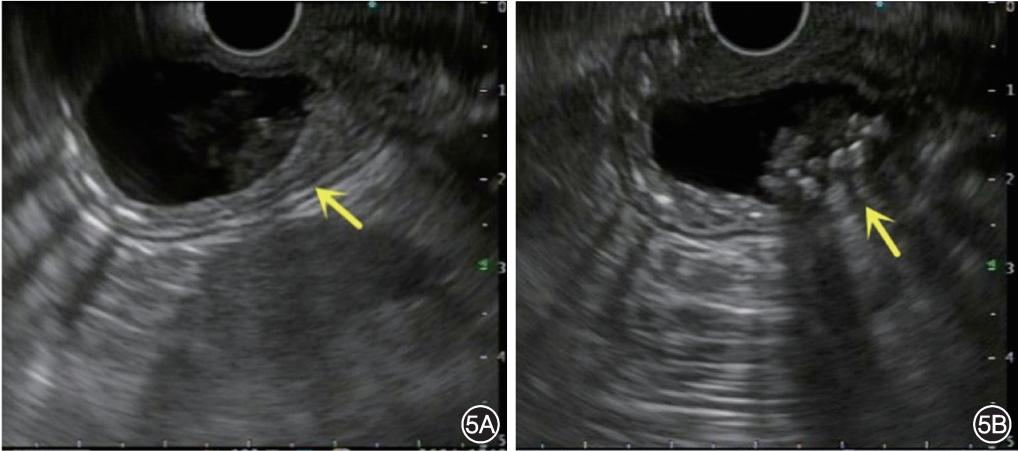

内镜超声检查(endoscopic ultrasonography,EUS):十二指肠降部可见一无回声囊性病变,囊壁表现为高低回声相间的7层管壁结构,囊内可见多发高回声影(图5)。结合患者病史及MRCP、EUS等检查结果,临床诊断:十二指肠囊性重复畸形(duodenal duplication cysts,DDC),急性胰腺炎(轻症)。给予抑酸、抑制胰酶分泌、抗感染、补液等治疗,患者因个人原因不考虑外科手术及内镜下囊肿切开引流治疗,腹痛好转后出院。随访至今患者无不适表现。

图5 内镜超声检查十二指肠降部可见一无回声囊性病变(黄色箭头所示) 5A:囊壁表现为高低回声相间的7层管壁结构;5B:囊内可见多发高回声影